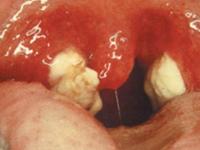

链球菌性咽炎怎么治疗?

现在朋友们不太注意自己身体,让自己的身体处于不健康的状态,有很多朋友都会有咽炎这个病症,那么有的朋友会觉得自己的咽炎总是反反复复的,会特别容易复发,链球菌性咽炎让朋友们会非常困惑,应该怎么进行诊断呢?这是很多患者都想知道的,常见症状有咽部干燥、发痒等!严重影响患者健康的生活,而且不一治愈,那么遇到这种病症了应该怎么做呢?下面由我为大家讲解一下。